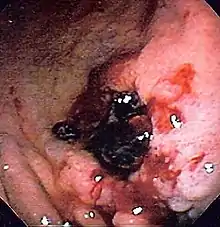

![]() Endoscopic still of esophageal ulcers seen after banding of esophageal varices, at time of esophagogastroduodenoscopy | |